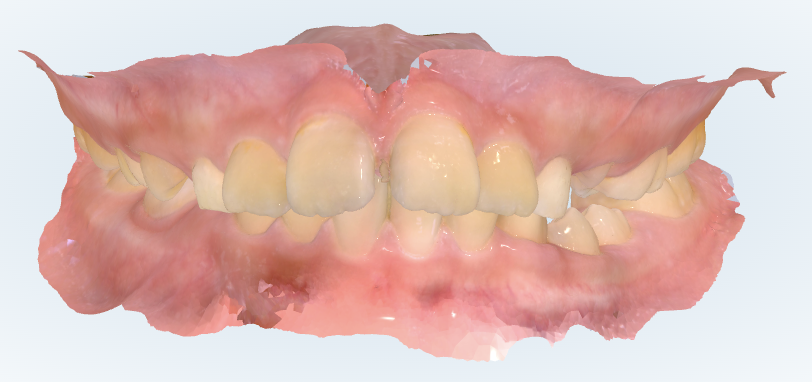

初診時の画像診断

出っ歯の歯並びをしています。

そうですね、実際に拝見すると、前歯の突出(出っ歯傾向)に加えて、奥歯の位置関係も前方にずれている状態です。